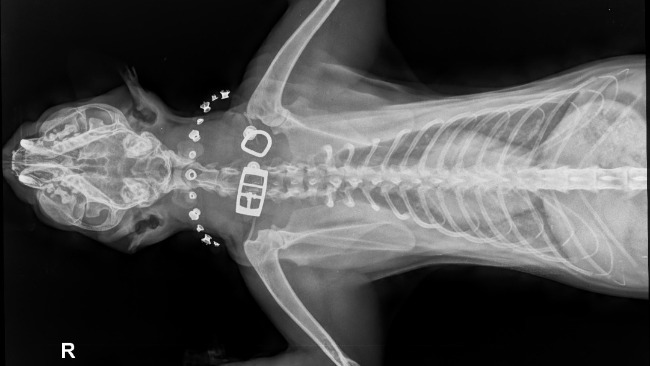

Wykonaliśmy również RTG w 4 projekcjach. Na pierwszy rzut oka wszystko wygląda dobrze, ale czekamy jeszcze na dokładny opis od specjalisty. Dodatkowo kupiłam Kokosowi leki odrobaczające na 3 miesiące, ponieważ jedną z możliwych przyczyn problemów mogą być pasożyty w płucach.

Poniżej dołączam zdjęcia RTG oraz potwierdzenia płatności.

Dostaliśmy opis od specjalisty. Kokos ma powiększone obie zastawki serca oraz wyciek w zatokach ( stąd ten świst u niego ). Będziemy podawać mu antybiotyk w zastrzykach i konieczna jest wizyta u kardiologa (ma odbyć się w przyszły wtorek) . Niestety to wszystko generuję kolejne koszty plus leki na serce które zapewne dostanie po wizycie u kardiologa. Z tego względu wciąż proszę o wpłaty i z całego serca dziękuję!